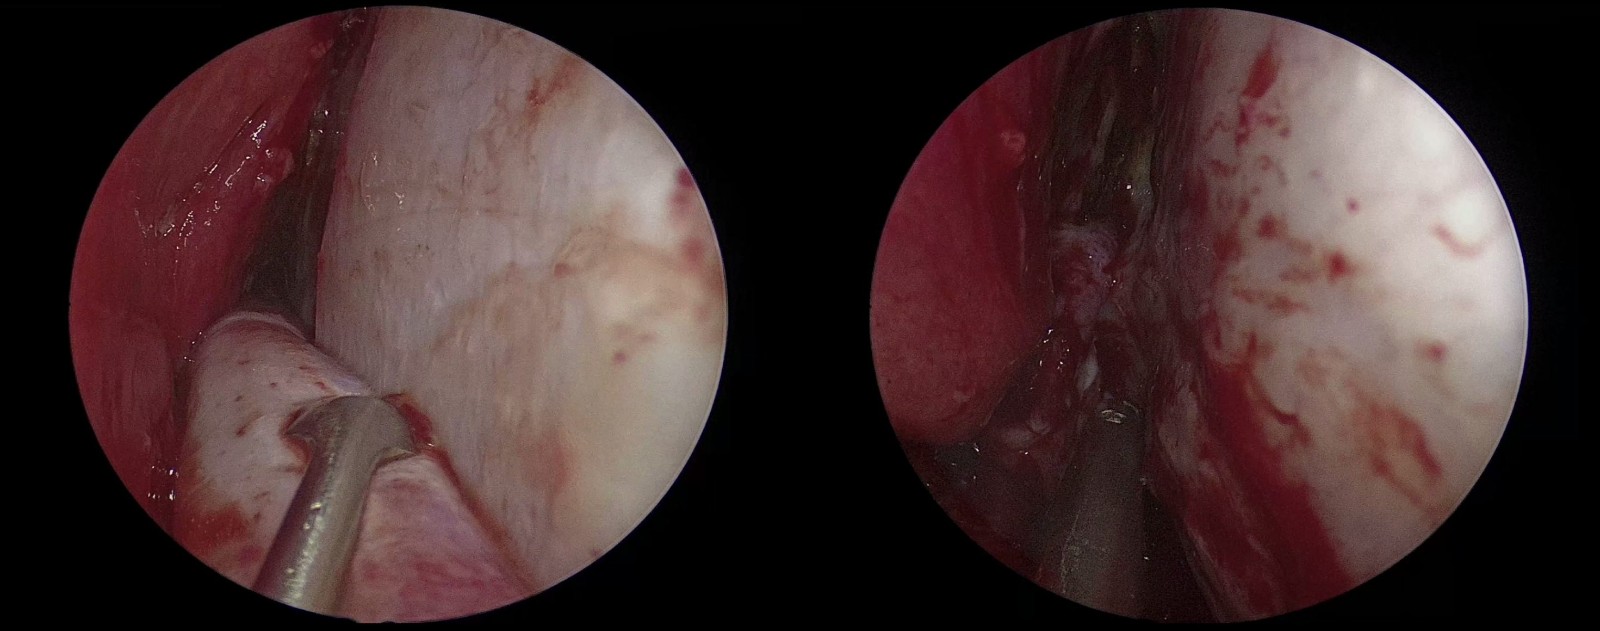

腫瘤切除

(1)制作帶蒂鼻中隔黏膜瓣

(2)切開鞍底硬膜(左)

(3)經垂體-視交叉間隙腫瘤全切(右)